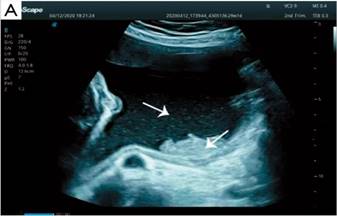

Otros métodos que se han utilizado en los últimos años para el diagnóstico prenatal de HI son la ecografía tridimensional (Figura 2) y tetradimensional en tiempo real.

Figura 2. Ecografía tridimensional. Partículas flotantes en el líquido amniótico (flechas). prenatal con genotipado rápido de SNP-array en sangre del cordón umbilical.

Fuente: 14